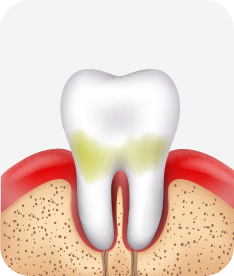

치주염(잇몸병)은 치아에 붙어있는 치석 및 세균 등에 의한 염증반응으로 잇몸뼈가 상실되는 질환을 말합니다.

초기에는 잇몸이 붓거나 잇몸에서 피가 나는 증상이 나타나며 계속 방치하면 치아를 발치해야 할 수도 있습니다.

치주치료는 이러한 치석 및 세균 등을 제거하여 잇몸뼈를 안정된 상태로 유지하는 시술을 말하며, 청담네오플란트에서는 치의학박사 / 전문의가 직접 시술하고 있습니다.

치주염 단계별 증상

건강한 상태

치아 주위의 잇몸이 핑크색을 띄며, 잇몸에서 피가 나지 않음.

스케일링을 6개월 ~ 1년 주기로 받고 올바른 칫솔질로 건강한 치주 조직을 유지

치은염 (초기~중기)

치아 주위의 잇몸이 붉게 부어 있으며, 칫솔질 등을 할 때 피가 남.

스케일링 주기의 조절이 필요할 수 있으며, 올바른 칫솔질을 시행하여야 함.

치주염 (중기~말기)

주기적으로 잇몸이 붓고 피가 나며, 욱씬하거나 우리한 통증이 나타남.

치주치료 및 정도에 따라 치주수술(잇몸수술)이 필요함. 향후 관리 정도에 따라 3~6개월 간격으로 내원하여 유지치료를 시행하여야 함.